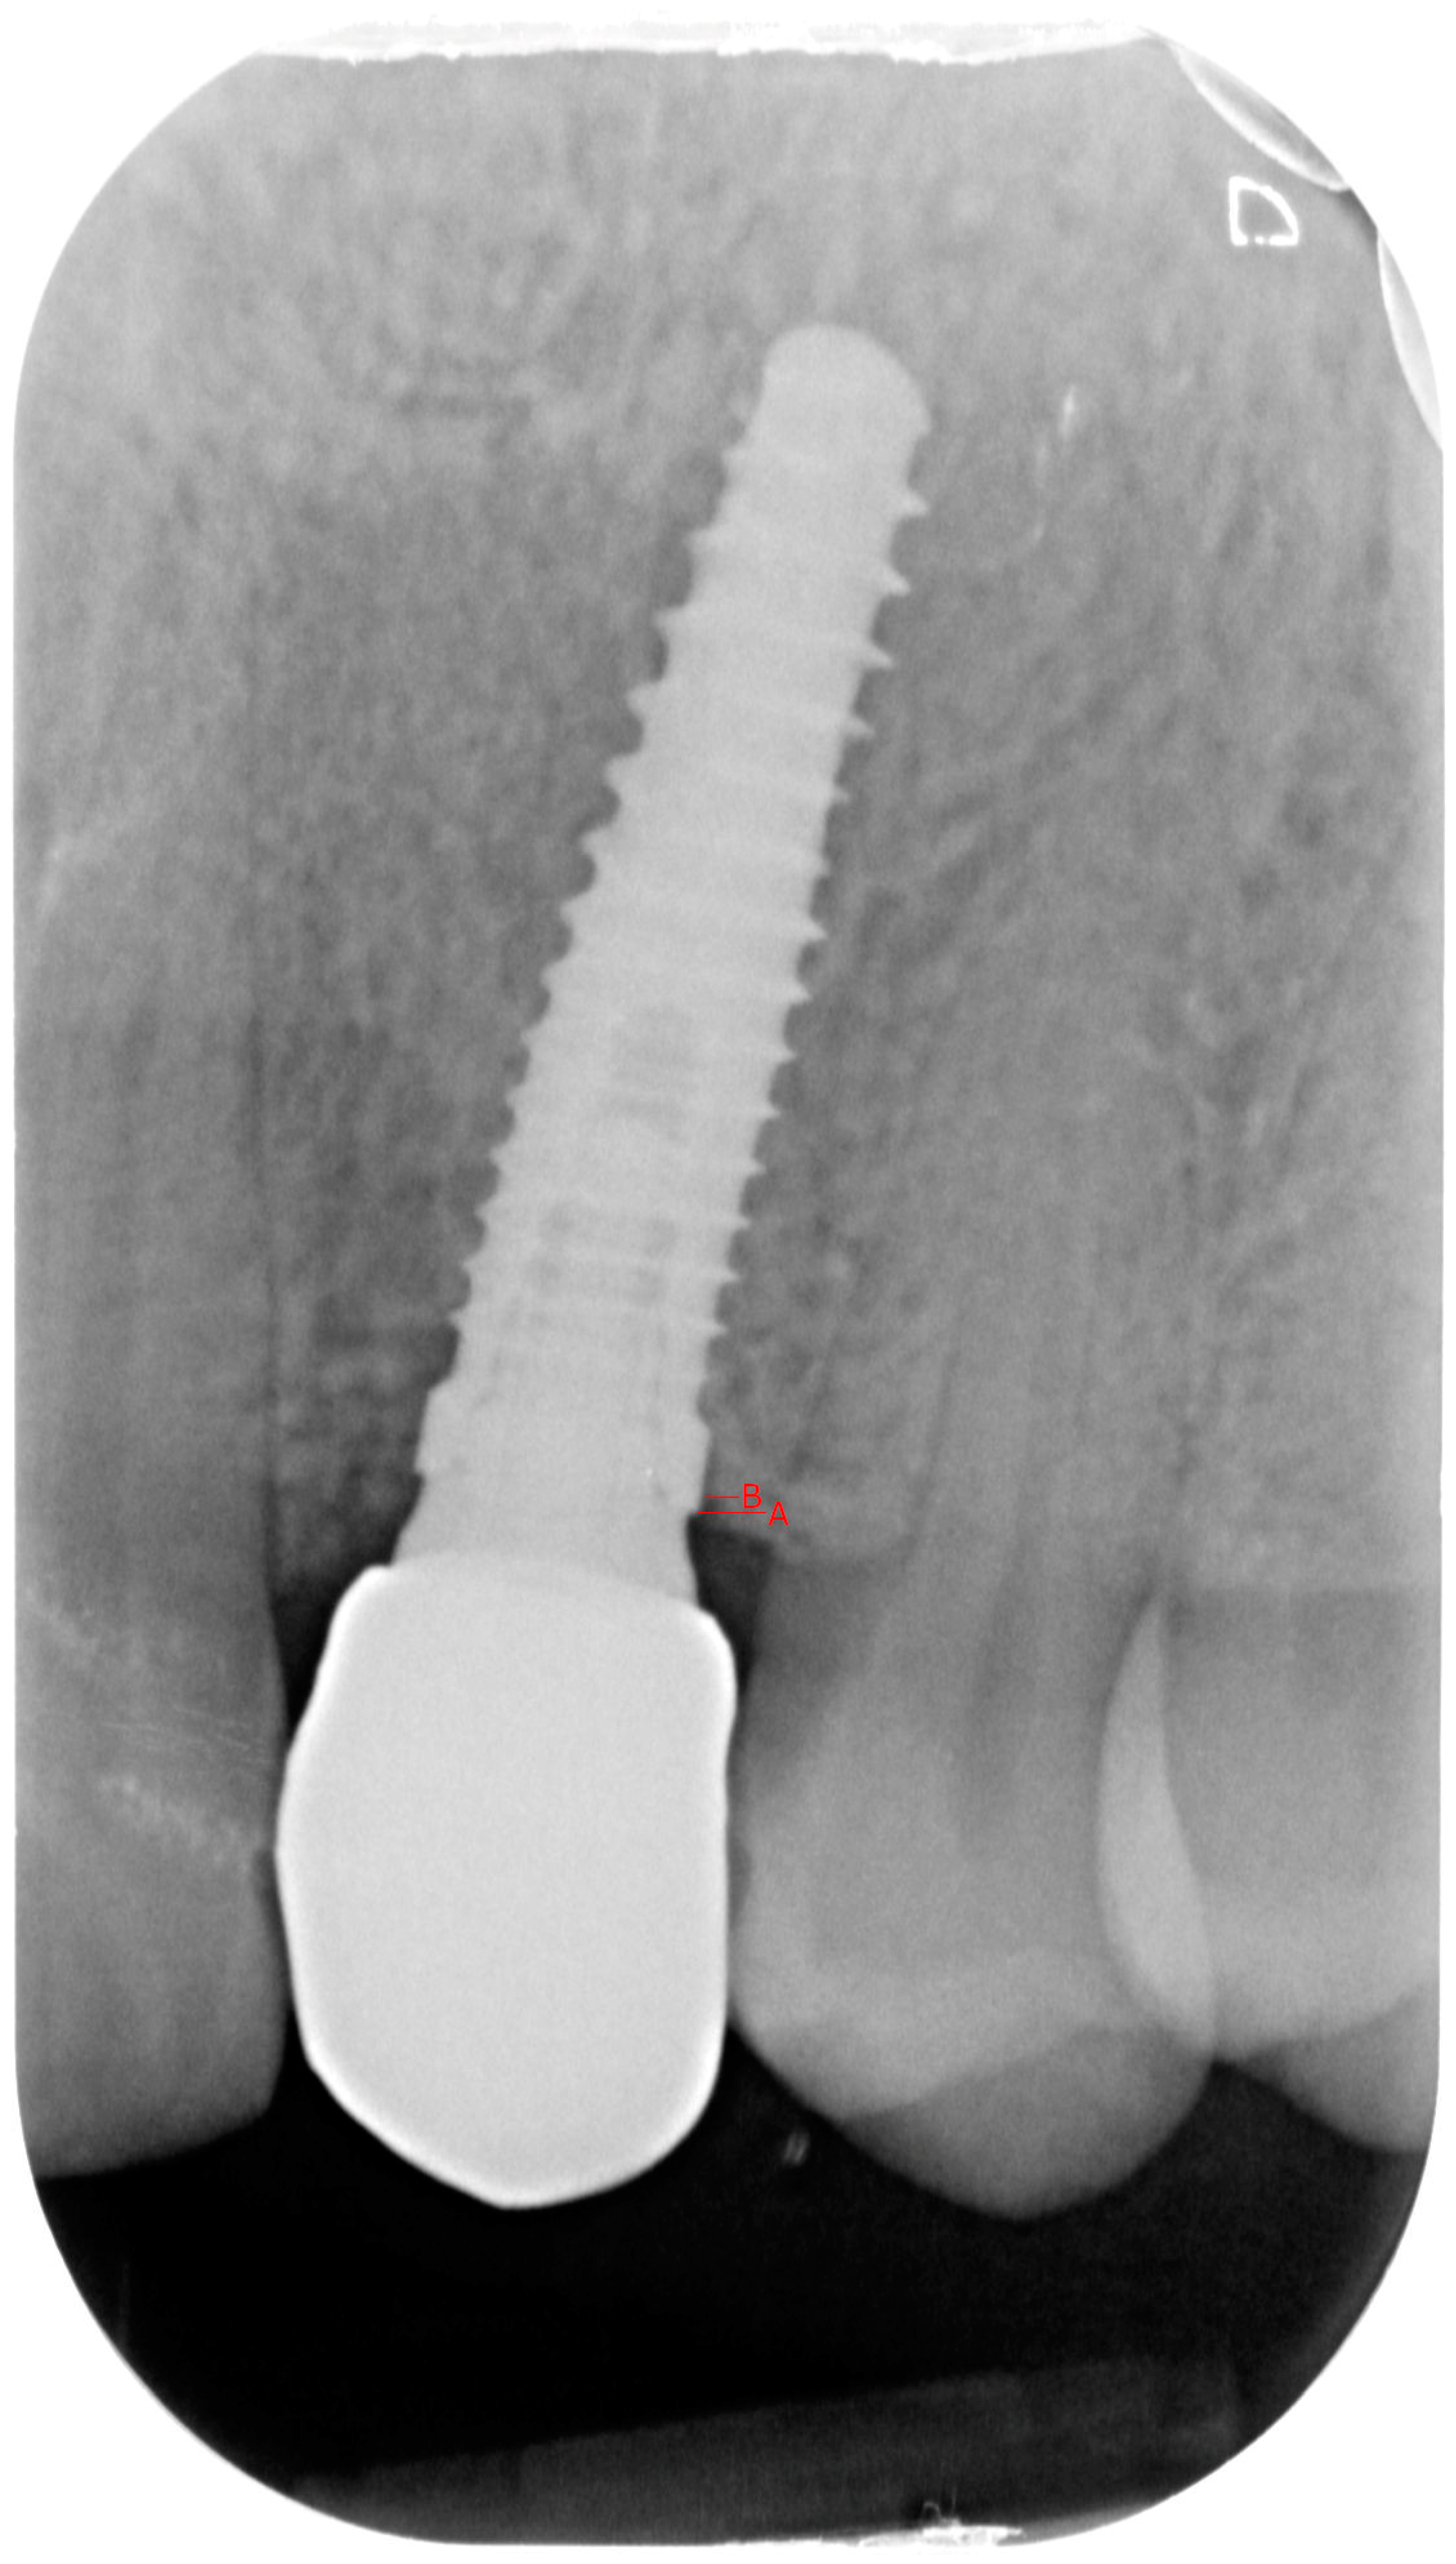

- Group 1: An implant-level impression adopting an open-tray impression technique was adopted using a polyvinylsiloxane impression material. After pouring the cast, an angled abutment was chosen, and a partially-veneered zirconia crown (limiting the veneering process to the vestibular surface) was obtained. At a second appointment, the abutment was screwed to the implant, and the crown was checked following the CMO (contact, margins, occlusion) acronym. The abutment was then manually screwed to the implant and secured at 25 Ncm. The access hole was closed with Teflon tape, and the crown was cemented with glass ionomer cement. (FujiCem 1, GC Europe, Leuven, Belgium) (Figure 1 and Figure 2).